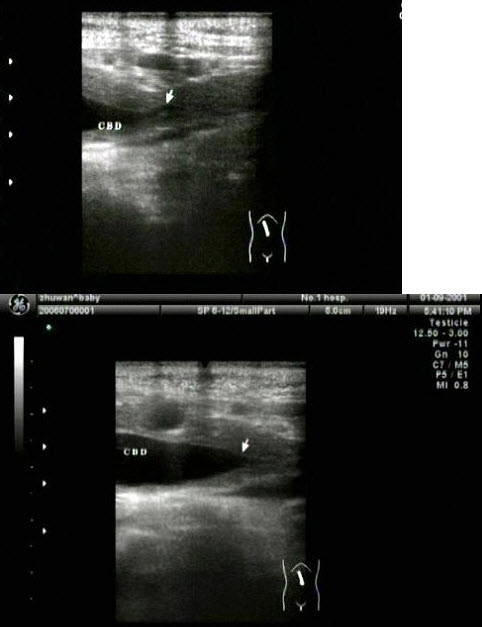

胆总管出现图中所示特点,称为()

A .双筒枪征

B .海鸥征

C .鸟嘴征

D .鼠尾征

E .平行管征

胆总管出现图中所示特点,称为()。

[单选题]胆总管出现图中所示特点,称为()。A . 双筒枪征B . 海鸥征C . 鸟嘴征D . 鼠尾征E . 平行管征

胆总管出现图中所示特点,称为()

[单选题]胆总管出现图中所示特点,称为()A . 双筒枪征B . 海鸥征C . 鸟嘴征D . 鼠尾征E . 平行管征

胆总管出现图中所示特点,称为( )。<br /><img border="0" style="width: 485px; height: 377px;

[单选题]胆总管出现图中所示特点,称为( )。A.双筒枪征B.海鸥征C.鸟嘴征D.鼠尾征E.平行管征

胆总管出现图中所示特点,称为()<img border="0" style="width: 407px; height: 305px;" src=&quo

[单选题]胆总管出现图中所示特点,称为()A.双筒枪征B.海鸥征C.鸟嘴征D.鼠尾征E.平行管征

胆总管出现图中所示特点,称为( )。<br /><img border="0" style="width: 485px; height: 377px;

[单选题]胆总管出现图中所示特点,称为( )。A.双筒枪征B.海鸥征C.鸟嘴征D.鼠尾征E.平行管征